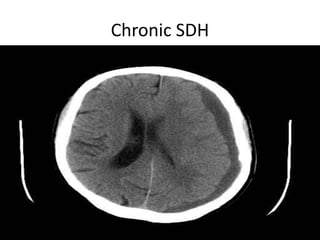

Chronic SDH

SDH